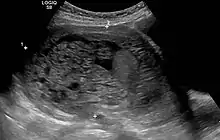

Molar pregnancy in ultrasound

The diagnosis is strongly suggested by ultrasound (sonogram), but definitive diagnosis requires histopathological examination. On ultrasound, the mole resembles a bunch of grapes ("cluster of grapes" or "honeycombed uterus" or "snow-storm").[14] There is increased trophoblast proliferation and enlarging of the chorionic villi, and angiogenesis in the trophoblasts is impaired.[15]